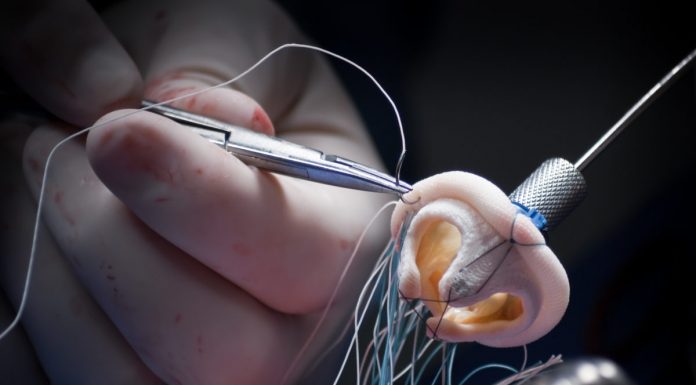

6 + 1 σημεία που πρέπει να γνωρίζω για να διαλέξω την ιδανική βαλβίδα καρδιάς

Στις επεμβάσεις αντικατάστασης των καρδιακών βαλβίδων χρησιμοποιούνται διάφοροι τύποι βαλβίδων. Παρακάτω αναλύονται 6+1 σημεία που θα βοηθήσουν τον ασθενή να επιλέξει ποια βαλβίδα είναι η κατάλληλη για την περίπτωσή του από τον κ. Χριστόφορο Σ. Κωτούλα, Καρδιοχειρουργό, Διευθυντή Κλινικής Ελάχιστα Επεμβατικής Χειρουργικής Καρδιάς Metropolitan...

ΙΑΣΩ Παίδων: Πρωτοποριακή επιτυχής επέμβαση τοποθέτησης πνευμονικής βαλβίδας σε 12χρονη καρδιοπαθή χωρίς εγχείρηση ανοιχτής καρδιάς

Η τεχνική της μη χειρουργικής αντικατάστασης (διακαθετηριακή) της πνευμονικής βαλβίδας με θεραπευτικό καθετηριασμό καρδιάς έχει καθιερωθεί τα τελευταία χρόνια ως η θεραπεία επιλογής σε ασθενείς με σοβαρή συγγενή καρδιοπάθεια στους οποίους κατά την διόρθωση της πάθησης με επέμβαση ανοιχτής καρδιάς γίνεται τοποθέτηση ενός βαλβιδοφόρου ...